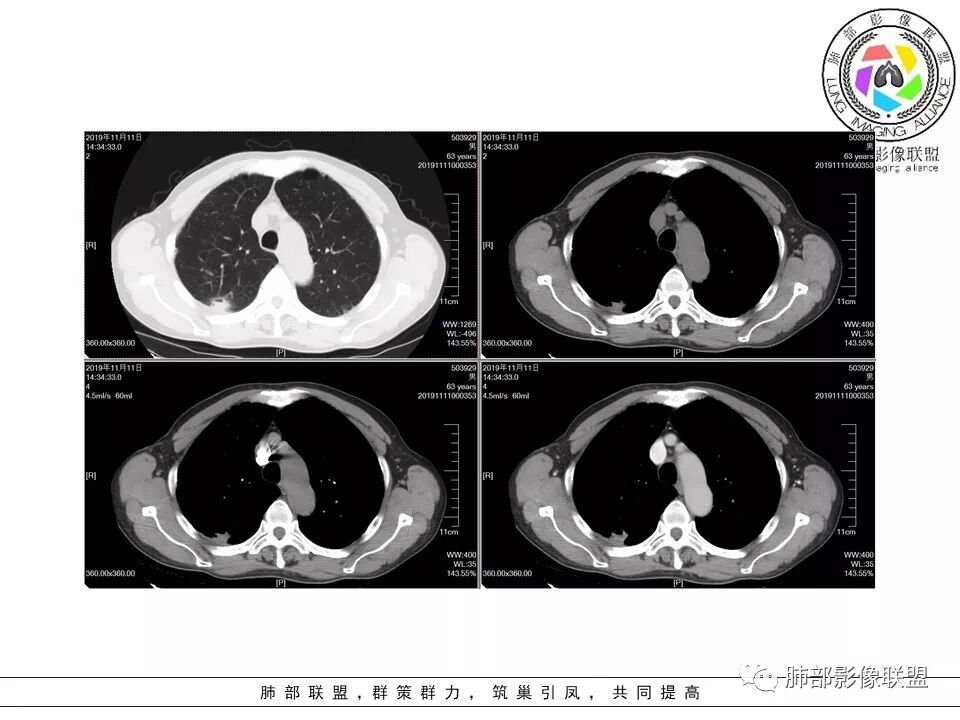

大雄:老年男性,有类风湿病史,长期服用激素,无阳性主诉CT示右肺上叶后段及左肺下叶基底段胸膜下多结节影,境界清晰,边缘毛糙,整体收缩,长轴与胸膜平行,增强扫描轻中度均匀强化。考虑炎性病变,建议查隐球荚膜多糖滴度试验

晕晕菜:患者中老年男性,体检发现肺部占位。既往既往有类风湿关节炎,长期口服激素胸CT:间隔旁肺气肿,右肺上叶后段胸膜下病变,与胸膜宽基底相连,局部胸膜明显增厚,病灶内可见空洞,病灶周围有散在卫星灶。左肺下叶背段胸膜下实变,病灶边界清楚,与长轴与胸膜平行,病灶周围可见软毛刺,纵隔窗可见病灶与胸膜呈糊墙征。 总体考虑良性病变。右上:结核?左下:隐球菌?

没意见:老年男性,明确有风免疾病背景,长期激素治疗,CT:双肺下叶外周多发结节,大部分宽基底胸膜相连,长轴垂直支气管,刀切平直,密度较为均匀,近心端空洞,强化程度目测略低,下肺背侧网格、磨玻璃、小蜂窝,考虑炎性结节,至于是感染还是风湿结节难度较大,需要结合临床来进一步确认

小赵:老年男性,类风湿及长期服药史。胸部CT所见右肺上叶及左肺下叶胸膜下多发病灶,右肺上叶病灶内见空洞及液平面,内壁光滑,周围散在条索及小结节样卫星灶,邻近胸膜增厚,增强扫描病灶轻度强化。左肺下叶病灶长轴平行于胸膜,周围见边界不清磨玻璃密度影,与邻近胸膜成糊墙改变。增强扫描病变成不均匀明显强化,内见强化血管影。诊断一元考虑双肺炎性病变,隐球菌可能。二元考虑右肺上叶结核,左肺下叶隐球菌感染,粘液腺癌待排。

菲菲菲:男,63,体检发现肺占位,既往类风湿性关节炎13年,双肺胸膜下多发斑片及结节影,右肺下叶病灶内见偏心性小空洞形成,周围有卫星灶,胸膜增厚,左肺下叶病灶轻度强化,纵隔内无肿大淋巴结,考虑炎性病变。隐球菌鉴别结核

一米阳光:双肺胸膜下多发结节病影,小结节融合,病灶与胸膜面平行,垂直支气管,边缘模糊,晕征,支气管进入堵塞,内见小空洞,增强均匀强化。结合病史,有类风湿病史,考虑炎性肉芽肿,隐球菌感染。鉴别,结核建议,穿刺,隐球荚膜抗原检查

破风5:胸部CT:右上叶胸膜下病变,与胸膜宽基底相连,累及胸膜,病灶内可见空洞,洞壁光滑,病灶周围有散在卫星灶。有类风湿激素口服历史,结核首先考虑。左肺下叶背段胸膜下实变,病灶边界清楚,与长轴与胸膜平行,血管伸入,纵隔窗可见糊墙征。考虑良性病变,隐球?总体,右上肺结核,左下肺隐球,CTD-ILD

流心明智:患者,老年男性,既往有类风湿关节炎,长期口服激素史。胸CT:间隔旁肺气肿,右肺上叶后段胸膜下病变,与胸膜宽基底相连,局部胸膜增厚,病灶内向肺门侧空洞,病灶周围卫星灶。考虑炎性病灶。左肺下叶胸膜下气肿背景边缘实变、边界清楚、有膨隆、滋养血管征,软毛刺、多结节融合、糊墙征。 总体考虑:良性病变,右上:结核?左下:隐球菌?左下鉴别Ca。

傅昌瑜:男,63,体检发现肺占位,既往类风湿性关节炎13年,RF升高,右下肺胸膜下结节,边缘多发斑片,右肺下叶病灶内见偏心性小空洞形成,相应层面胸膜增厚,左肺下叶两个结节,上面大点的结节位于胸膜下,似有支气管进入后截断,病灶轻度强化,病灶内见坏死区,纵隔内无肿大淋巴结。肺内病灶似乎不怎么类似,隐球菌应该是兄弟同心。肺内病灶考虑肉芽肿性病灶,有长期口服糖皮质激素史,首先考虑奴卡可能,鉴别隐球菌及结核这个妖怪。类风湿结节没有见过。

右上叶边缘收缩,宽基底与胸膜相连,胸膜增厚,附近索条,支持炎性

南边:糊墙,长轴与胸膜平行;边缘收缩+膨隆;脐凹征

常规:隐球菌与癌鉴别

脐凹征,高度提示恶性

因为其与胸膜的关系与右上叶的不一致,所以不能一元论